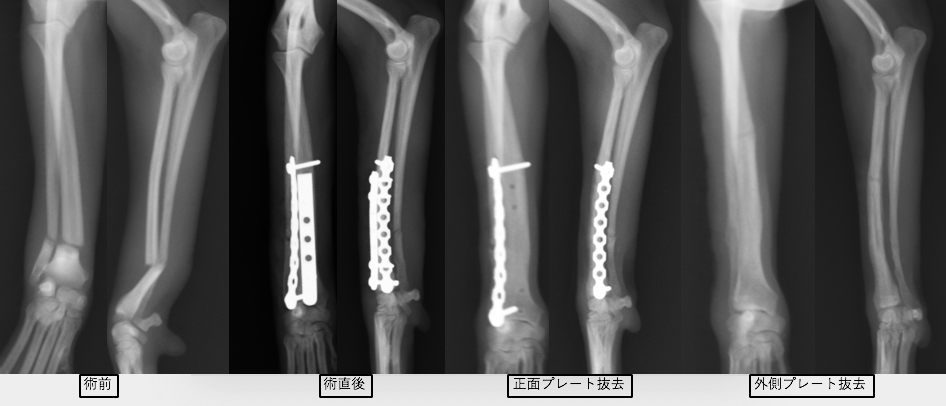

チワワの橈尺骨骨折です。1.5mmスクリューを使用しています。

体重約1kgの2歳のティーカッププードルで、超小型の1.1mm径スクリューを使用しました。

2症例ともに橈尺骨遠位端骨折です。骨折端が短すぎて直線のプレートが入らない(スクリューを3本入れる必要があります)ため、正面にT字型のプレートを使用しています。